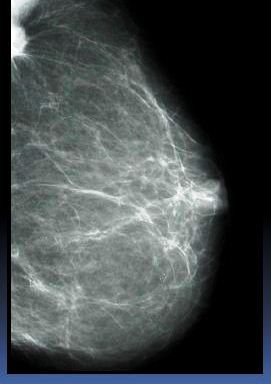

Kazuistika 2

- Klientka s nálezem nepravidelného zastínění při bazi sin

- Na kontrolním snímku správně zhotoveném není patrná

- Dobré vytažení!!! Komprese!!!